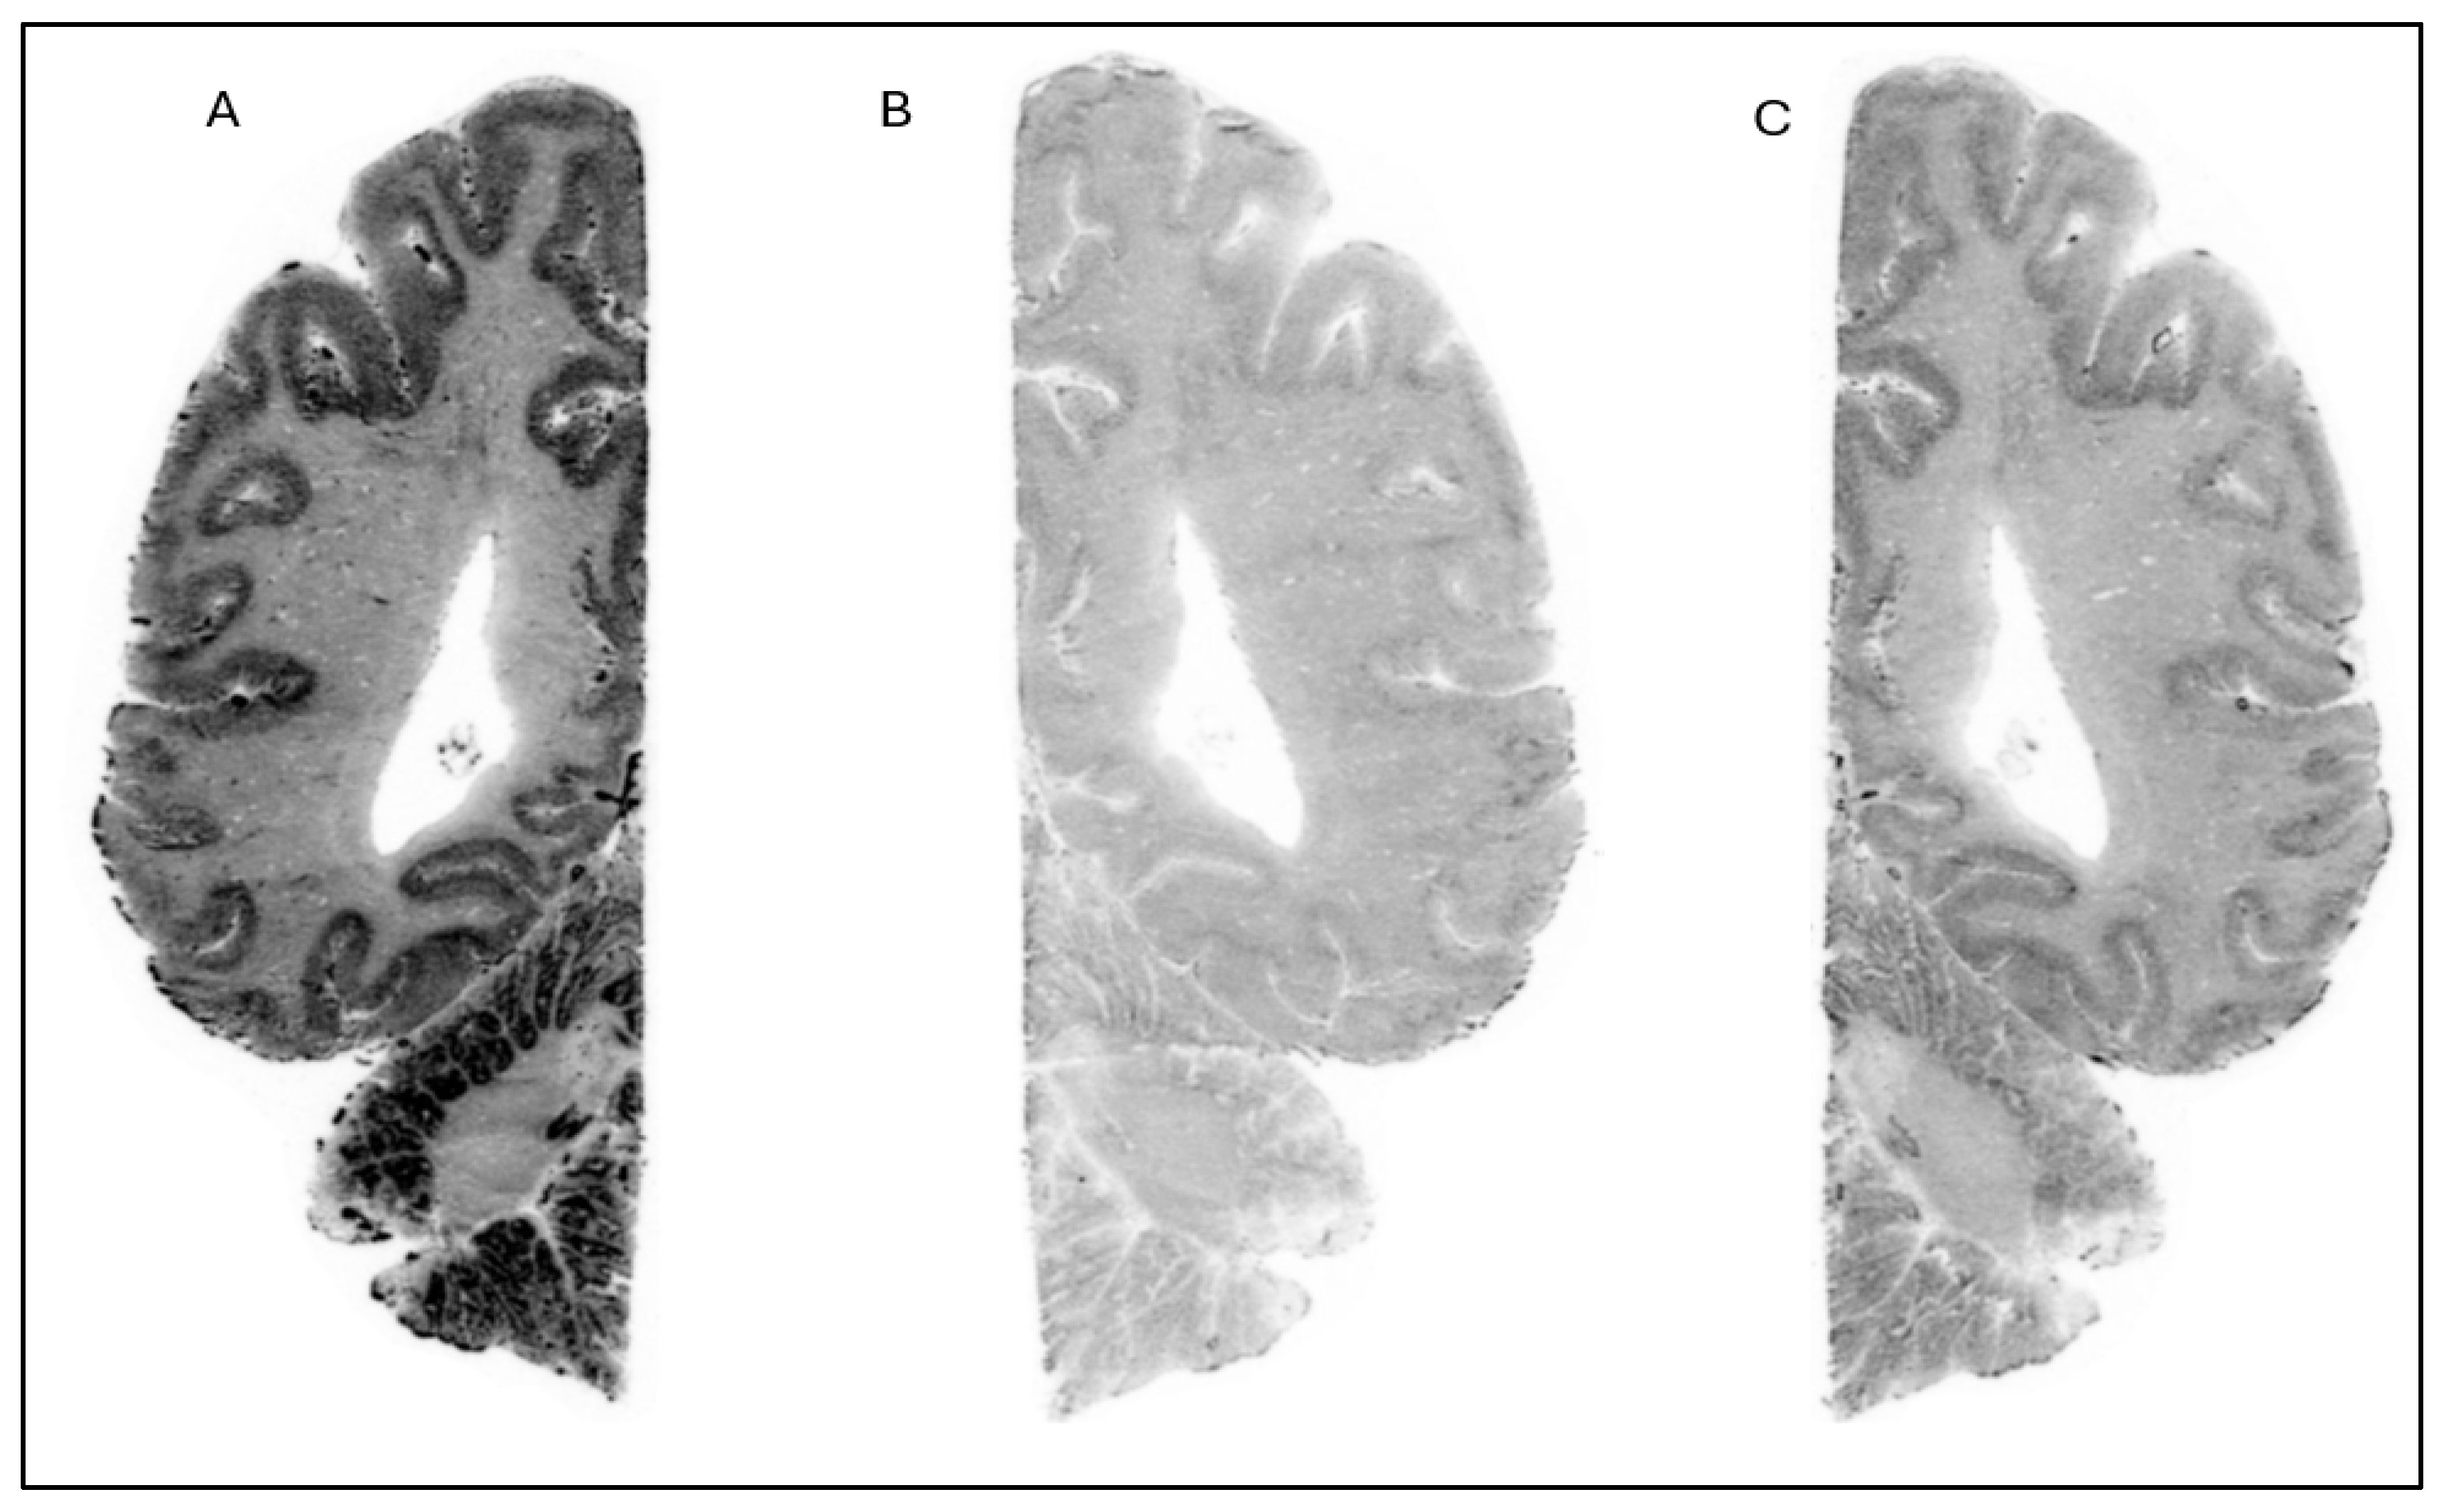

The in vitro ARG studies aimed to assess the binding characteristics of the compounds; [18F]1 displayed clear binding in brain slices from NHP (Figure 2) and human (Figure 3). The binding was effectively blocked by an excess of cold Compound 1 (self-block) as well as Compound 3 (heterologous block), indicating that its interaction with brain tissue is likely specific. However, pre-incubation with 0.1 µM of PFE-360 [20], another structurally different LRRK2 kinase inhibitor, did not significantly reduce the binding of [18F]1 in a human brain slice (Figure 4). This could indicate that [18F]1 exhibited limited specificity but more likely that the concentration of PFE-360 used may have been suboptimal, as Compound 2 demonstrated significant blocking activity at 10 µM.

Figure 3. Autoradiograms of horizontal slices of a human brain labeled with [18F]1 at baseline condition (A) and during incubation with Compound 1 (10 µM) (B) and cold Compound 3 (10 µM) (C).